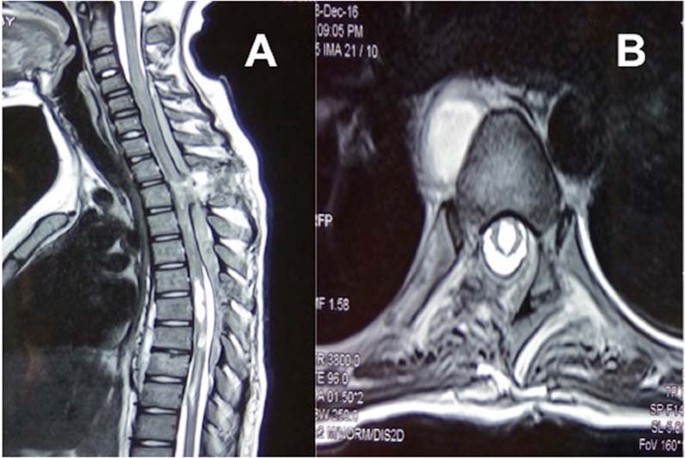

Once home thoracic spine surgery patients can expect a recovery time of 3 to 6 months. The syrinx is filled with cerebrospinal fluid CSF. The dressings will be removed several days after. If u also have chiari usually the PFD. The surgical procedure has to be performed timely since if postponed for a longer period of time the affected structures can be damaged irreversibly and the surgery will not be. There I was diagnosed with what was likely an intramedullary spinal ependymoma.

Based on the diagnosis and the likely cause of the syrinx a neurological surgeon may recommend a procedure to normalize the cerebrospinal fluid flow. Symptoms may improve even if the syrinx remains the same size or is reduced only slightly. Decompression surgery returns the flow of spinal fluid to normal and usually resolves the condition. Recovery from the actual surgery varies from 4 to 6 weeks depending on your general health. A syrinx cannot be removed from the spinal cord since it is embedded. What many people dont realize is that even with a.